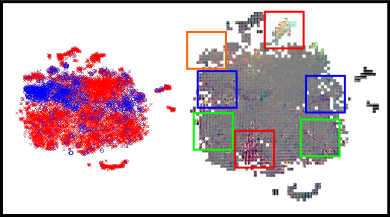

CNNs can be interpreted as models that transform the input images into a feature representation in which classes can be separated by the linear model in the last layer. The topology of such a space will depend on the ability of the deep learning features to characterize the inputs. Hence, if features are sufficiently good to differentiate each type of input, at least two well separated regions would be visually identified. Due to the high dimensionality of the feature space, a method is needed to embed multidimensional vectors in a 2D space, while preserving the pairwise distances of the points. The -distributed stochastic neighbor embedding (-SNE) was recently introduced for this purpose (Van Der Maaten, 2014). We followed this approach to study the complementarity of each characterization method, and to qualitatively assess how their integration contribute to improve their original discrimination ability. Figure 14 presents the -SNE mappings of the DIARETDB1 test samples for each characterization approach and for our combined feature vector. The CNN descriptors corresponds to those learned in Experiment 1. The figure also includes a visual representation of the organization of the patches in the embedding space. In general, it is possible to see that the ensemble approach groups the majority of the true positive candidates within a single neighboring area. By contrast, the individual characterization strategies are not able to achieve a single cluster but rather obtain two–in the case of the deep learned features–or more–using the hand crafted features.

Detailed regions of the embeddings are depicted in Figure 15. This allows better visualization of particular scenarios such as the patches around the true red lesions, the false positive candidates located in the vascular structures, the artifacts due to speckles of dirt in the lens–which are typical of the images in DIARETDB1–and the false detections within the optic disc. In general, it is possible to observe that CNN features are able to better characterize the orientation and the visual appearance of the true lesion candidates, while the hand crafted features can detect the less obvious lesions under low contrast conditions. The ability of the CNN features to discriminate orientations are more evident when dealing with vascular structures. The hand crafted approach, by contrast, is only able to capture the overall size of the vessels and their intensity properties. When combining both strategies, the main advantages of each of them are maintained. The robustness against artifacts is evident for both the deep learning based and the hand crafted features, as these false positive candidates are grouped together into separate clusters from the true lesions. A similar behavior is observed when dealing with false candidates within the optic disc area.

In general, the integration of both the deep learned and the hand crafted features significantly improved results compared to using either approach separately. In a per lesion evaluation, the combined approach achieved a consistently higher CPM value both in the e-ophtha and DIARETDB1 test sets, and also a higher per lesion sensitivity for FPI=1, which corresponds to a clinically relevant number of false positives (Niemeijer et al., 2010). These values are also higher than those obtained by two recently published baseline methods that were evaluated on the same data set. A similar behavior is observed when evaluating the method on a per image basis. The combined approach improved the performance obtained by each characterization approach separately, meaning that the integration of both sources of information obtains a better characterization of the lesion candidates and, consequently, a more accurate detection of the individual lesions. This is supported by the extensive analysis presented in Section 4.3. Despite the fact that sufficiently deep CNNs are known to be able to learn any function of arbitrary complexity, the lack of data with lesion-level annotations does not allow our network to identify the same properties that the hand crafted features do. Nevertheless, in the analysis of the -SNE mapping presented for each method (Figures 14 and 15) it is possible to see that the CNN has the ability to characterize fine-grained details such as the orientation of the lesion that are ignored by the manually selected descriptors. On the other hand, the hand crafted features have the ability to discriminate other low contrast lesions (Figure 15), specially hemorrhages (Figure 8(b)). As a result, the ensemble approach is able to outperform each individual alternative, improving performance for detecting both MA and HE simultaneously. Due to the high cost of accurately annotating small lesions, we hypothesize that this observation will continue to stand in the near future.